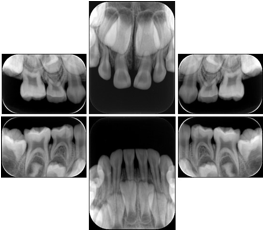

2. A patient requests cosmetic surgery to enhance their facial appearance. The case requires consultation between an orthodontist in New York and an oral surgeon in California. The cephalometric series of 2D projections constructed from a volumetric CT data set that is used for the discussion is arranged by a Structured Display for transfer between the two practitioners.

Cephalometric Series Structured Display

Figure OO-2. Cephalometric Series Structured Display